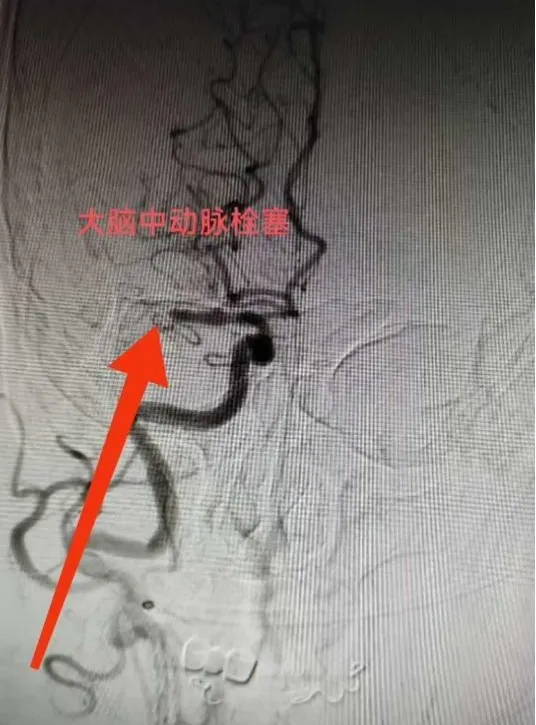

“必须立即进行脑动脉取栓手术!”神经内科王文杰主任了解患者详情后当机立断。与家属充分沟通并获得同意后,患者被迅速送入介入治疗室。术中造影显示,患者右侧大脑中动脉M1末端完全闭塞。术中造影发现患者多发动脉硬化、狭窄,血管迂曲明显,情况复杂,手术难度较高。且患者病情进展加重,王文杰、于弋水决定在局麻下为患者急诊动脉机械取栓。根据患者血管特点,选用合适导管行“血栓抽吸术”,仅一次操作即完整取出暗红色血栓,原闭塞血管血流瞬间恢复至最高分级(mTICI 3级),从穿刺到血管完全再通仅用50分钟。